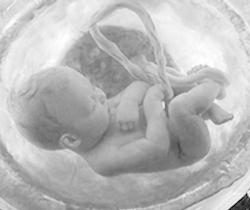

INFECCIONES PERINATALES

Infecciones transcervicales

El feto se infecta mediante la inhalación de líquido amniótico infectado hacia los pulmones poco antes del parto o al atravesar el canal del parto infectado

Infecciones transplacentarias

Estas infecciones se dan en cualquier momento de la gestación o, en algunos casos como sucede en la hepatitis B o el VIH, durante el parto por transfusión maternofetal